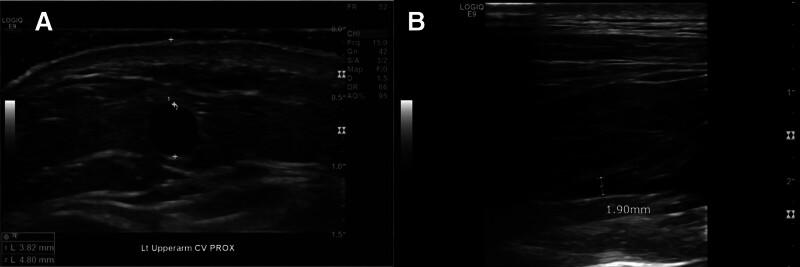

The surgical plans could not be determined solely based on preoperative ultrasound findings. In Patient 1, AV access using an artificial graft with the brachial artery as the inflow and the brachial vein as the outflow in a forearm loop configuration was considered as the primary option. In Patient 2, the cephalic vein drainage was unclear with ultrasound due to the clavicle.

The operation was performed with a transverse incision just below the elbow. Before the anastomosis, we conducted intraoperative fluoroscopic venography through the surgically exposed median cubital vein using a small amount of diluted contrast media to assess the overall venous drainage system in the upper arm.

The initial surgical plans based on ultrasound findings were modified through intraoperative fluoroscopic venography. In Patient 1, the distal anastomosis was redirected to the median cubital vein, thereby preserving the deep vein. In Patient 2, fluoroscopic venography enabled the successful creation of AV access using an autologous vein instead of a graft by directly visualizing the cephalic vein drainage. At early follow-up, both accesses achieved successful maturation; however, long-term outcomes could not be fully assessed, and no access-related complications were observed during the observation period.